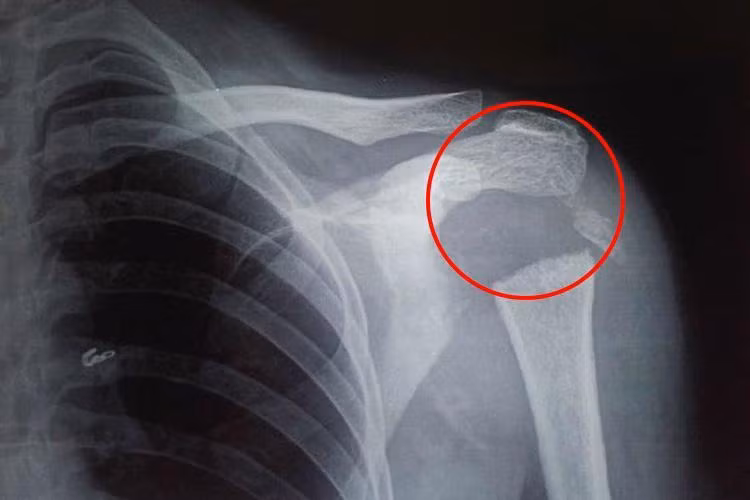

Sau khi tiến hành chụp chiếu, tia X cho thấy phần xương tròn kết nối cánh tay với vai của cô đã tiêu biến khiến nó chỉ còn một mảnh nhỏ. Các bác sĩ tại Viện Khoa học Y khoa Pondicherry ở Ấn Độ đã cho xét nghiệm nhiễm trùng, nội tiết tố cũng như trao đổi chất, tuy nhiên mọi thứ đều ở trạng thái bình thường.

Theo báo cáo trường hợp của Tạp chí Y khoa Anh, vùng xương dài ở cánh tay trên của người phụ nữ đã biến mất. Ban đầu, đội ngũ y bác sĩ nghi ngờ do bệnh về thần kinh gây ra nhưng cô hoàn toàn không hề có triệu chứng liên quan. Sự thiếu hụt các triệu chứng thần kinh khiến gây ức chế cho cơ thể, do vậy các bác sỹ chẩn đoán cô mắc chứng Gorham-Stout, một căn bệnh cực kỳ hiếm gặp khiến xương tiêu biến.

| Sau khi tiến hành chụp X quang cùng nhiều xét nghiệm khác, các bác sĩ chẩn đoán cô mắc chứng bệnh hiếm gặp có tên Gorham-Stout. |